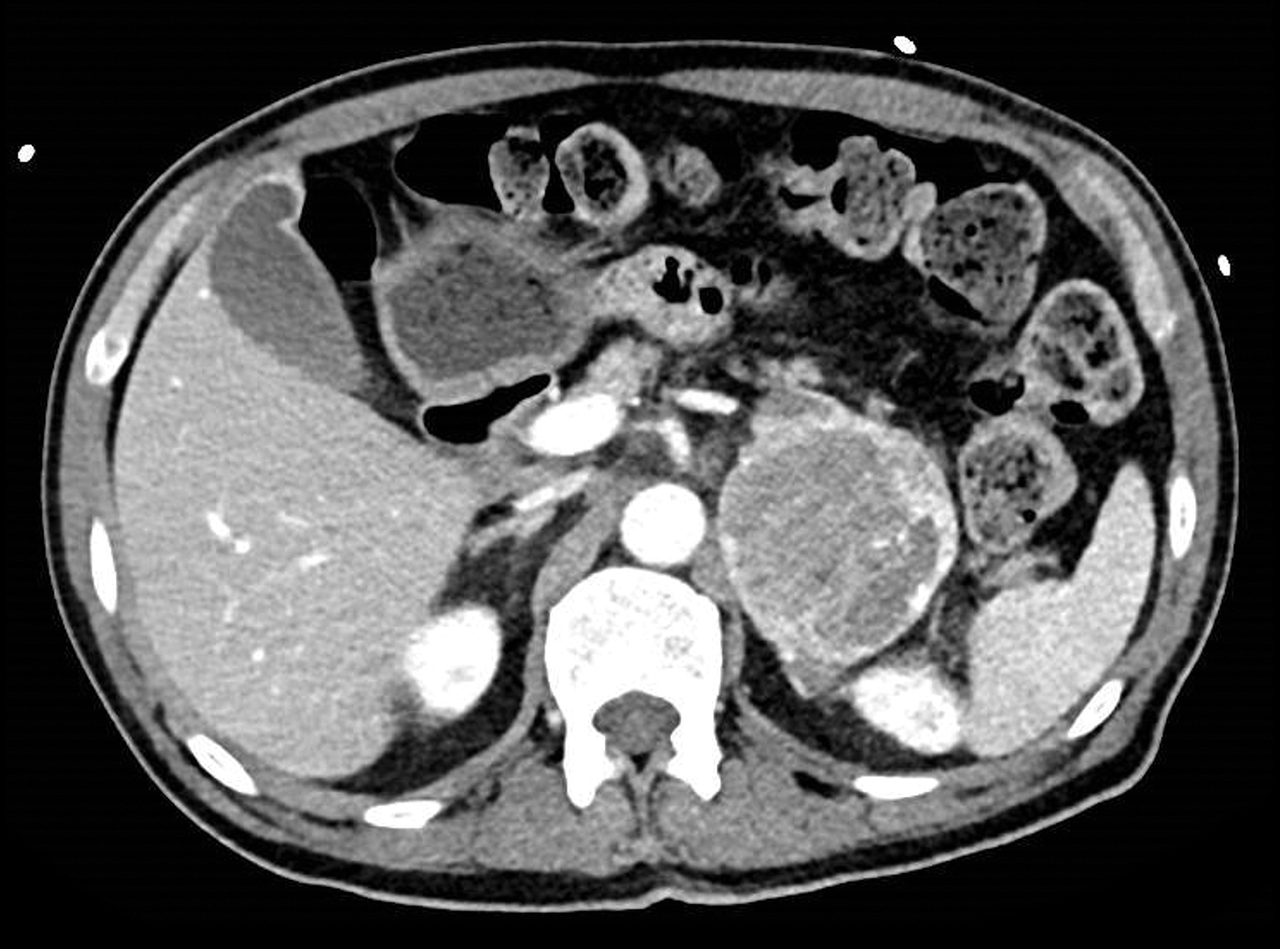

Un homme de 57 ans, diabétique de type 2, est hospitalisé pour des douleurs lombaires et un amaigrissement.

Sa pression artérielle est à 160/80 mmHg et son pouls à 110/mn.

Quel est votre diagnostic ?